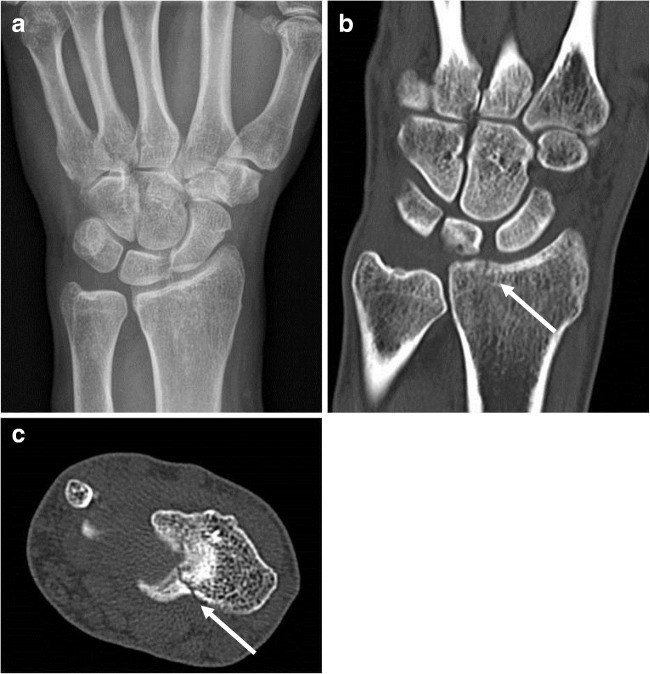

Fig. 4.

Missed fracture on CR with treatment upgrade after CT. A 45-year-old male with a painful left wrist after fall on an outstretched arm and with swelling at the level of the lunate, but no hematoma or pressure pain. CR was negative for fractures (a). Based on these images, both clinicians and the observers proposed conservative treatment with a pressure dressing. CT demonstrated an intra-articular, distal radius fracture (arrows, b and c). All observers upgraded to cast treatment. The patient was finally treated with cast for 3 weeks